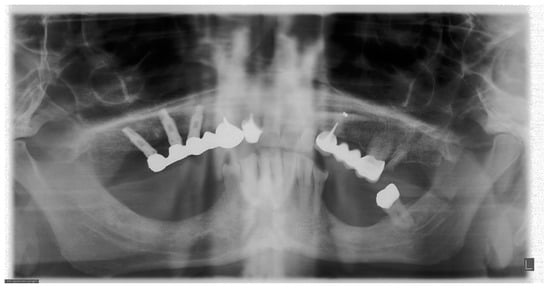

5. The Importance of Head Orientation

6.1. Symmetry

6.4. Aspect of Upper Teeth Root Apexes

6.5. Position of the Cervical Spine